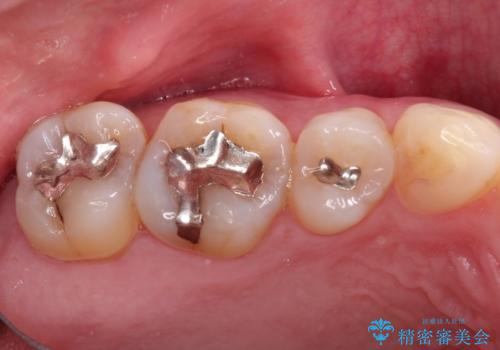

メタルフリーの治療 メタルインレーからセラミックインレーへ

- メタルフリーの治療を希望され来院されました。

セラミックインレーに治療を行っております。